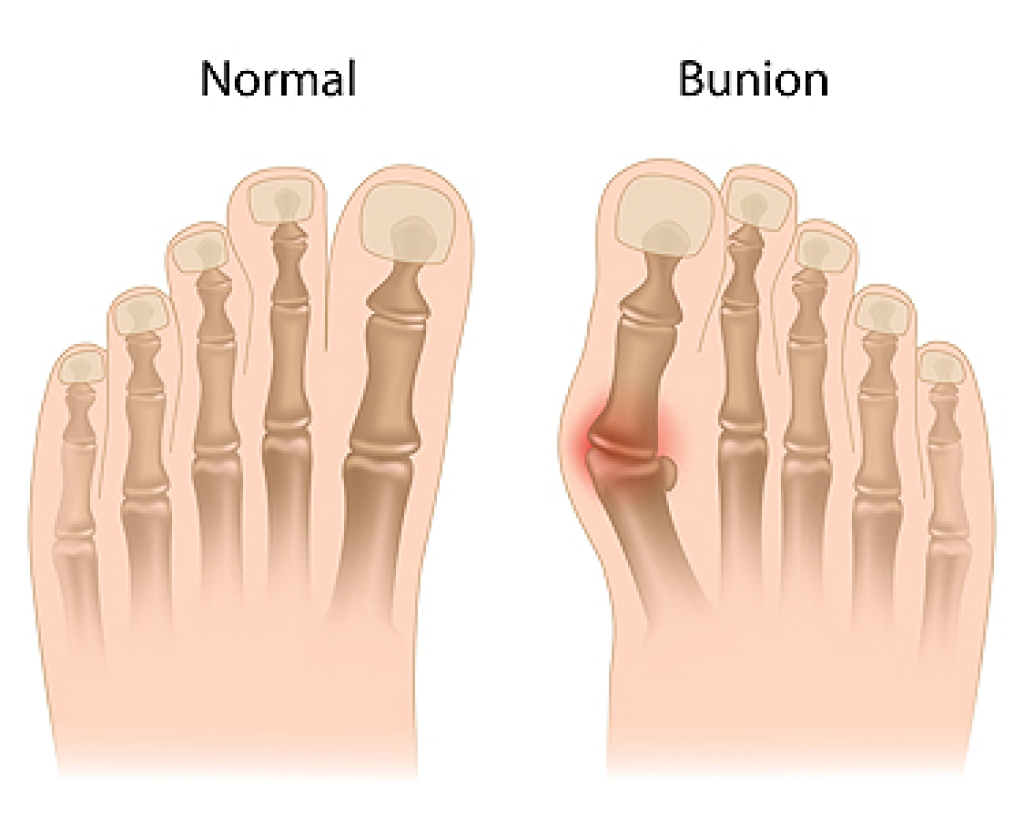

The foot condition known as a bunion is a progressive bone disorder. It is a lump on the side of the big toe that can happen from wearing shoes that do not have enough room in the toe area. Bunions may also occur due to genetic reasons. A bunion is considered a deformity and severe bunions can cause the other toes to shift toward each other. Some patients can develop bunions from overpronation, and this causes the foot to roll inward and can also be related to having flat feet. If the body's weight is unevenly distributed, an abnormal foot structure may develop which could lead to a bunion developing. Hypermobility is a condition that causes the bones to move more than they normally would and this may also result in a bunion. If you have a bunion, it is suggested that you confer with a podiatrist who can determine the proper plan of treatment for you.

A bunion is formed of swollen tissue or an enlargement of boney growth, usually located at the base joint of the toe that connects to the foot. The swelling occurs due to the bones in the big toe shifting inward, which impacts the other toes of the foot. This causes the area around the base of the big toe to become inflamed and painful.